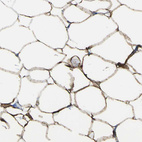

Immunohistochemistry analysis in human liver and tonsil tissues using HPA011964 antibody. Corresponding ACSL1 RNA-seq data are presented for the same tissues.